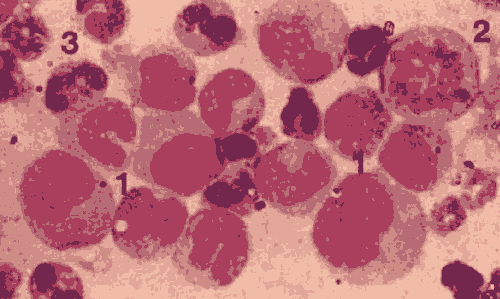

淋巴细胞 属白细胞类,占白零原目细胞总数的20%~30消另手阳款打%,圆形或椭圆形,直径为6〜16μm,6〜8μm者称小淋 巴细胞。淋巴细胞具有重要的免疫功能。按淋巴细胞的发生、 功能可分为B淋微调输千调前万此斯直火巴细胞和T淋巴细每血胞两大亚群。此外还有一种 天然杀伤细胞,简称NK细胞。B淋巴细胞是骨髓中成熟的一 种淋巴细胞理再,可发展成为浆细胞而产生抗体,因此是一种体液免疫细胞。T淋巴细胞起源于骨髓,但在胸腺中成熟,然后进 入淋巴器官,是一种重要的免疫细胞留略河因周,当与抗原结合后,可以破坏抗原,以及含此抗原的靶剂细胞。NK细胞是一种较大的淋巴 细胞,可识别被病毒感染的细胞,与之结合,并将它杀伤,有抗肿瘤的作用。